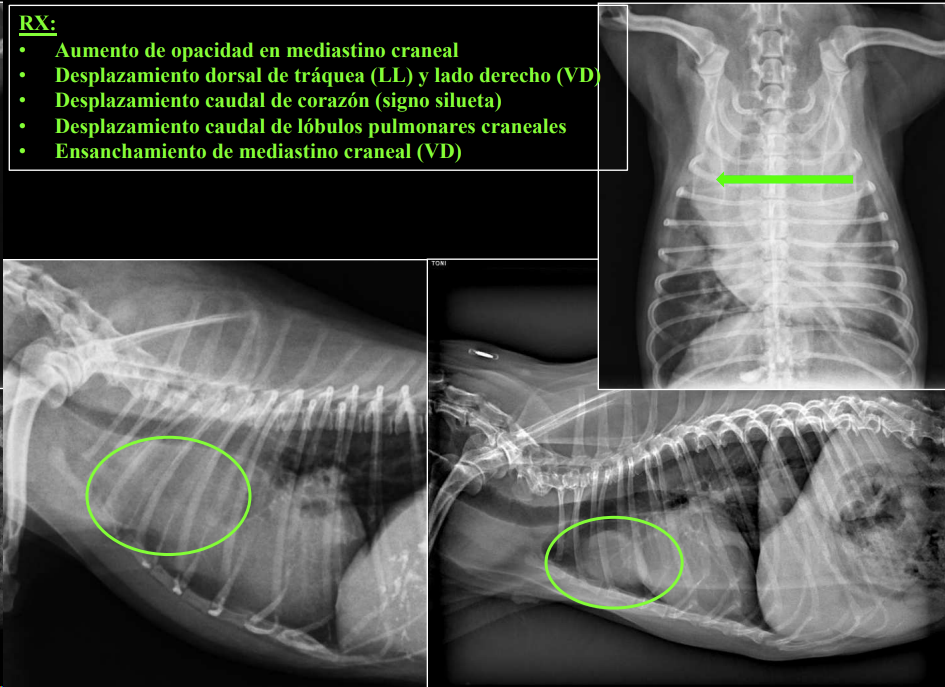

3. Alteraciones de anchura del mediastino craneal

Causas:

- Derrame mediastínico.

- Masas mediastínicas (craneodorsales, hilares, caudodorsales, caudoventrales, craneoventrales).

- Linfomas en gato, timomas en perros.

CLASIFICACIÓN DE MASAS MEDIASTÍNICAS

Craneodorsales: alteraciones esofágicas, aneurisma aórtico, hematoma, tumor base cardíaca/neurogénico, absceso, granuloma, lesión vertebral.

Desplazamiento traqueal dorsal por masa en el mediastino craneal

Hiliares/Perihiliares: alteraciones esofágicas, tumor base cardiaca, linfoadenopatía traqueobronquial, masa tiroidea ectópica.

Masa de opacidad tejido blando que desplaza la traquea y la bifurcación bronquial.

Craneoventrales: linfoma, timoma, tumor tiroideo, histiocitosis, lipoma, fibrosarcoma, linfoadenopatía esternal o craneal, absceso, aneurisma auricular.